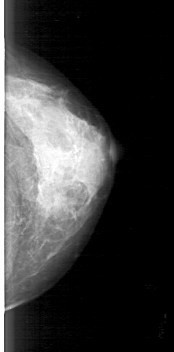

D_4185_1.RIGHT_MLO

ics_version 1.0

filename D-4185-1

DATE_OF_STUDY 2 5 1994

PATIENT_AGE 42

FILM_TYPE REGULAR

DENSITY 3

DATE_DIGITIZED 2 6 1999

DIGITIZER HOWTEK 43.5

LEFT_MLO LINES 4771 PIXELS_PER_LINE 2326 BITS_PER_PIXEL 12 RESOLUTION 43.5 NON_OVERLAY